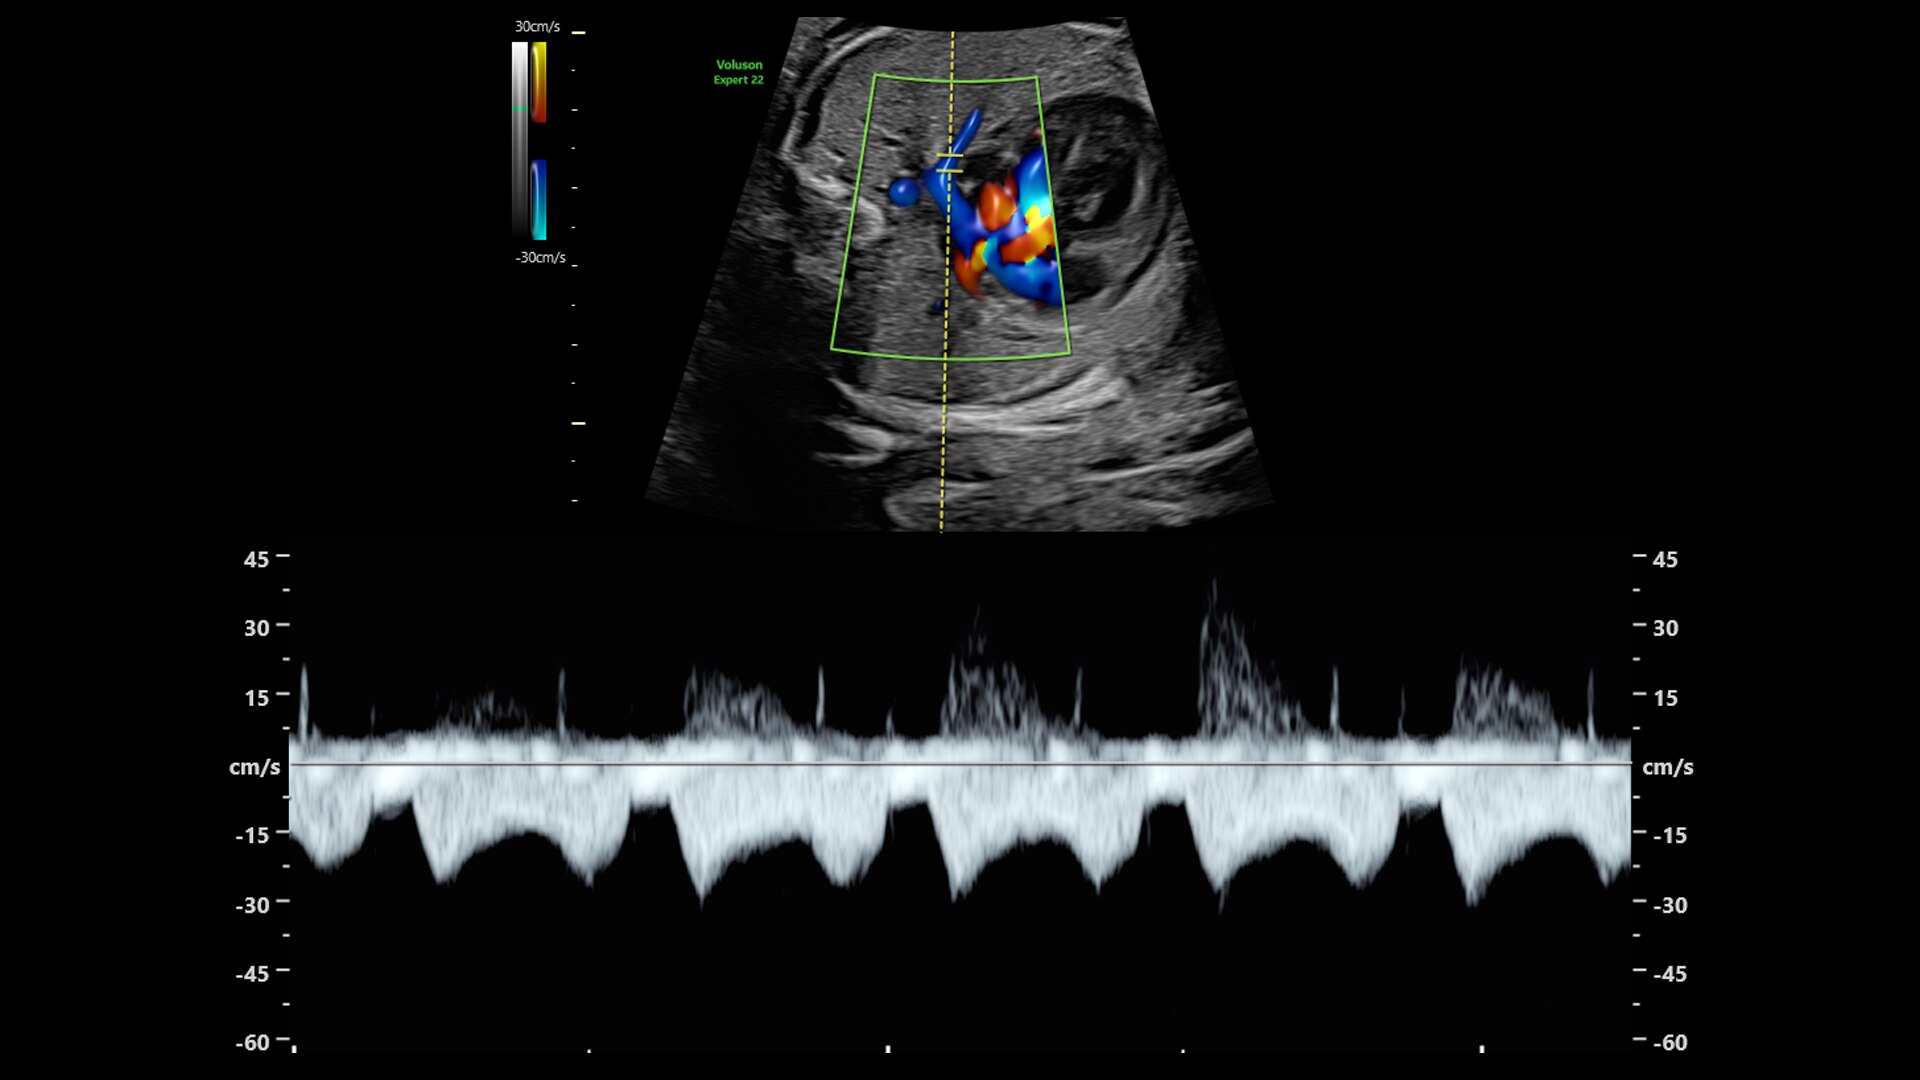

DOPPLER IMAGING

Beyond Basic Blood Flow

Voluson is pushing imaging boundaries to make blood flow assessment faster and easier. Our advanced technologies, including Graphic flow, Radiantflow, Slowflow, and Radiant imaging, increase resolution and sensitivity in color and pulsed wave Doppler for unprecedented clarity

Hemodynamic Visualization

Provides a graphical representation of the trajectories of the blood cells in real-time to visualize complex blood flow quickly and clearly, helping you to differentiate normal from abnormal hemodynamics